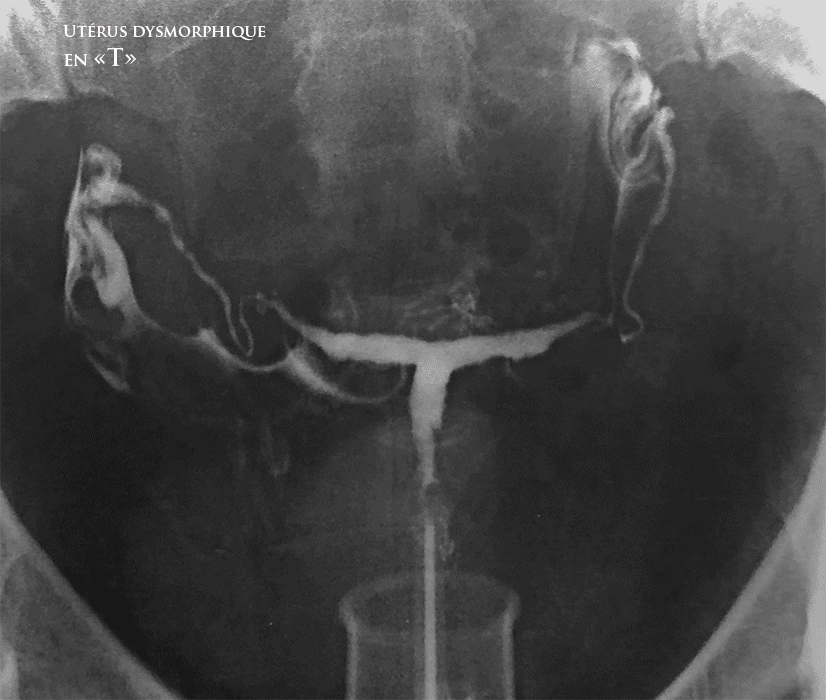

- Utérus dysmorphique en "T" se caractérise par une impotrtant épaississement du myomètre au niveau des bords latéraux et le fond utérin.

- L'utérus en " T "se caractérise par une cavité utérine étroite, en forme de T due à l'épaisseur exgérée des parois utérines latérales. Le corps utérin occupe les 2/3 de la longeur de l'utérus et le col utérin (cervix) occupe le 1/3 de cette longuer.

Imagerie par HSG (Hystérosalpingographie) et par échographie pelvienne.